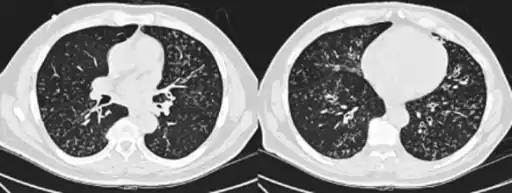

High-resolution computed tomography images of the lower chest in a 16-year-old boy with diffuse panbronchiolitis

The diagnosis of DPB requires analysis of the lungs and bronchiolar tissues, which can require a lung biopsy, or the more preferred high resolution computed tomography (HRCT) scan of the lungs.[7] The diagnostic criteria include severe inflammation in all layers of the respiratory bronchioles and lung tissue lesions that appear as nodules within the terminal and respiratory bronchioles in both lungs.[4] The nodules in DPB appear as opaque lumps when viewed on X-rays of the lung, and can cause airway obstruction, which is evaluated by a pulmonary function test, or PFT.[6] Lung X-rays can also reveal dilation of the bronchiolar passages, another sign of DPB. HRCT scans often show blockages of some bronchiolar passages with mucus, which is referred to as the "tree-in-bud" pattern.[7] Hypoxemia, another sign of breathing difficulty, is revealed by measuring the oxygen and carbon dioxide content of the blood, using a blood test called arterial blood gas. Other findings observed with DPB include the proliferation of lymphocytes (white blood cells that fight infection), neutrophils, and foamy histiocytes (tissue macrophages) in the lung lining. Bacteria such as H. influenzae and P. aeruginosa are also detectable, with the latter becoming more prominent as the disease progresses.[4][5] The white blood, bacterial and other cellular content of the blood can be measured by taking a complete blood count (CBC). Elevated levels of IgG and IgA (classes of immunoglobulins) may be seen, as well as the presence of rheumatoid factor (an indicator of autoimmunity). Hemagglutination, a clumping of red blood cells in response to the presence of antibodies in the blood, may also occur. Neutrophils, beta-defensins, leukotrienes, and chemokines can also be detected in bronchoalveolar lavage fluid injected then removed from the bronchiolar airways of individuals with DPB, for evaluation.[4][9]